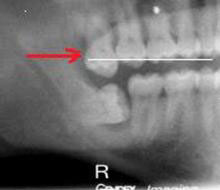

Конечная цель врача при эндолечении – расширить, отмыть и запломбировать канал зуба на всю длину, ровно до верхушки. При этом плохо, если есть «перелет» или «недолет». Как правильно определить точную длину канала и почему это важно? «Перелет» или попадание пломбировочного материала за верхушку зуба в окружающую кость нежелательно, т.к. может привести к различным осложнениям. «Недолет», запломбированный не до верхушки зуб чаще всего приводит к возникновению гранулем и кист, т.к. остается необработанная зона, в которой поселяется «плохая» микрофлора. Как же точно определить длину канала? Для этого врач стоматолог пользуется рентгеном и/или (лучше безусловно «и») апекслокатором. С рентгеном я думаю все понятно, многие с ним сталкивались. Стоматолог вводит в канал инструмент, отмечает на нем длину и делает снимок. После этого он может эту длину объективно откорректировать. Апекслокатор – очень удобный прибор, этакий эндодонтический парктроник. Он подключается к инструменту, которым доктор расширяет канал, и при приближении кончика инструмента к верхушке корня начинает пищать, чем ближе, тем интенсивнее… точь-в-точь как парктроник в автомобиле. Таким образом стоматолог может в реальном времени контролировать глубину погружения инструмента с точностью до долей миллиметра. Причем первые апекслокаторы достаточно сильно врали, особенно если канал не был сухой… Современные приборы дают очень точные результаты, практически сведя к минимуму необходимость постоянного обращения к рентгену. При этом все же золотой стандарт эндодонтии – использование апекслокатора на протяжении всего лечения, плюс 3 рентгеновских снимка для каждого зуба: статус до лечения, во время (как правило, с инструментами или штифтами, погруженными на всю длину всех каналов), после окончания лечения каналов и реставрации зуба. Причем роль этих снимков скорее документальная.